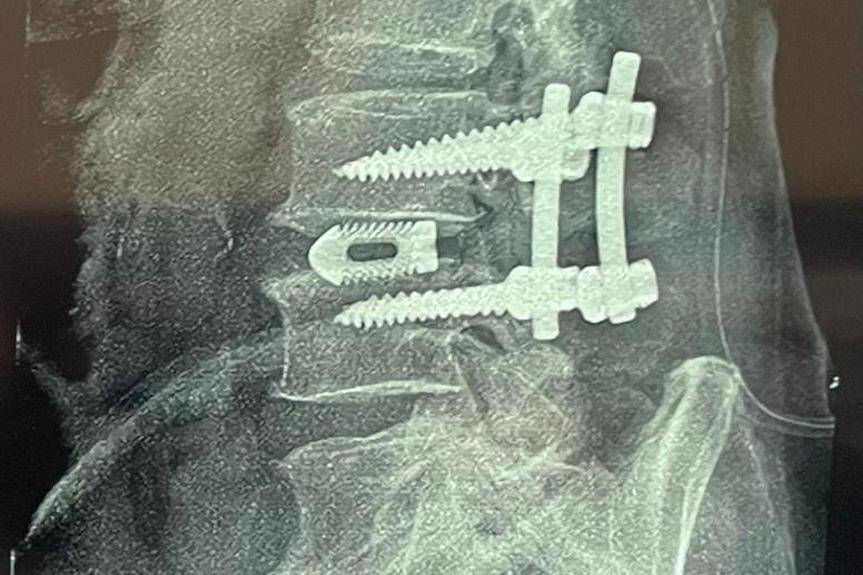

W Oddziale są leczeni chorzy ze zdiagnozowanymi zespołami uciskowymi kręgosłupa lędźwiowego i szyjnego w przebiegu choroby dyskowej, choroby zwyrodnieniowej kręgosłupa. W zależności od rodzaju patologii, dojścia operacyjnego do miejsca objętego chorobą, stosowane są różne techniki operacyjne, w tym: ALIF, OLIF , XLIF, TLIF, PLIF z zastosowaniem nowoczesnych implantów.

Stosowanie nowoczesnych technik leczenia w chirurgii kręgosłupa przyczynia się do szybkiego powrotu do zdrowia, skrócenia absencji chorobowej.